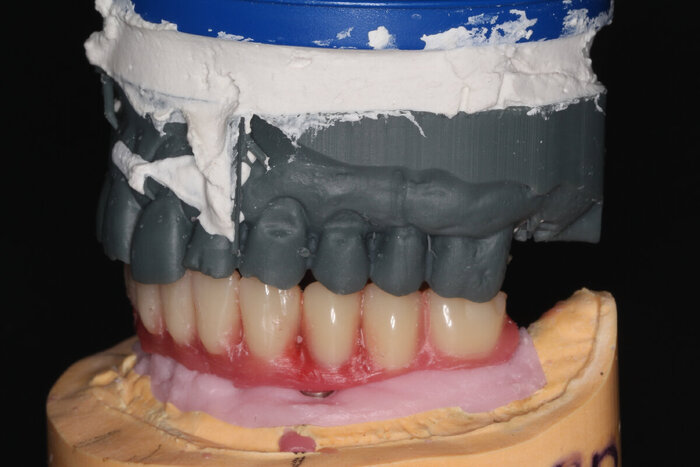

Я уже писала о распечатанном прототипе, точно повторяющем верхнюю челюсть пациента - вот, теперь показываю его вам.

Доктор сразу видит то, что идеально протез на примерке не сядет. Но на то она и примерка - что бы выявить все нюансы и скорректировать моменты.

Посмотрим на восковой протез нижней челюсти поближе.

Примеряем в полости рта. Посмотрим, даст мне робот за зубы человека на пряники или пощадит.

Теперь наносим фиолетовую коррекцию, что бы техники оценили весь масштаб поправок.